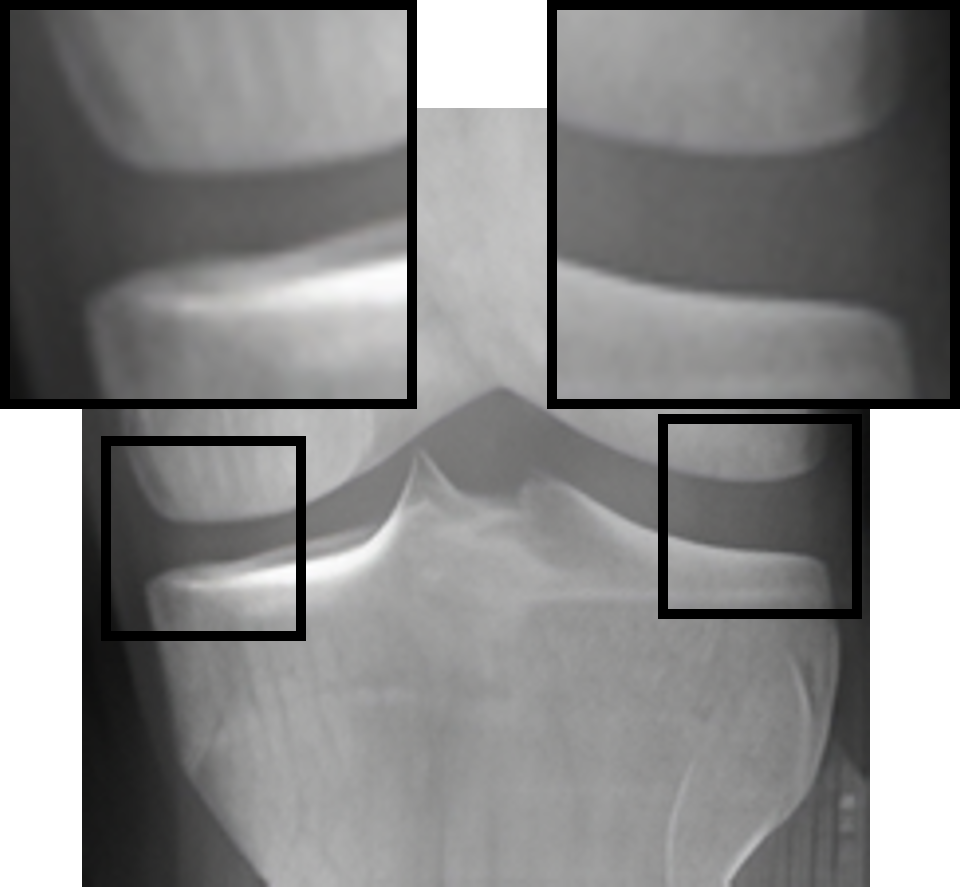

Table 2: Visualization of the synthesized intermediate frames

Input image Synthesized intermediate framessuperscriptSynthesized intermediate frames\stackrel{{\scriptstyle\text{Synthesized intermediate frames}}}{{\makebox[284.52756pt]{\rightarrowfill}}} Input image

xSsubscript𝑥𝑆x_{S} xS(φη=0.25)subscript𝑥𝑆subscript𝜑𝜂0.25x_{S}(\varphi_{\eta=0.25}) xS(φη=0.5)subscript𝑥𝑆subscript𝜑𝜂0.5x_{S}(\varphi_{\eta=0.5}) xS(φη=0.75)subscript𝑥𝑆subscript𝜑𝜂0.75x_{S}(\varphi_{\eta=0.75}) xTsubscript𝑥𝑇x_{T}

KL-0 KL-1∗∗ KL-2∗∗ KL-3∗∗ KL-4

[Uncaptioned image] [Uncaptioned image] [Uncaptioned image] [Uncaptioned image] [Uncaptioned image]

• *

The morphed areas of each frame were highlighted within black boxes, the red arrow and red circle indicate the locations of JSN and osteophyte formation, respectively. A shorter arrow indicates a smaller joint space (i.e., a narrower distance between the tibia and femur), while a larger circle indicates more osteophytes.

• **

The expected labels.

4.2 Visualization of the synthesized intermediate frames

In Table 2, we show the source image xSsubscript𝑥𝑆x_{S}, the target image xTsubscript𝑥𝑇x_{T}, and their intermediate frames (i.e., xS(φη=0.25)subscript𝑥𝑆subscript𝜑𝜂0.25x_{S}(\varphi_{\eta=0.25}), xS(φη=0.5)subscript𝑥𝑆subscript𝜑𝜂0.5x_{S}(\varphi_{\eta=0.5}) and xS(φη=0.75)subscript𝑥𝑆subscript𝜑𝜂0.75x_{S}(\varphi_{\eta=0.75})), which is crucial in understanding how the source images evolve into their registered state. The progressive alignment is quantified by the parameter η𝜂\eta evenly divided into 0.25, 0.5, and 0.75, which represents the extent of transformation at each stage of KOA, corresponding to KL-1, KL-2, and KL-3, respectively. As can be seen, xS(φη=0.25)subscript𝑥𝑆subscript𝜑𝜂0.25x_{S}(\varphi_{\eta=0.25}) shows the initial stage of the morphing process where the morphs are minimal and closely resemble the source image. For xS(φη=0.5)subscript𝑥𝑆subscript𝜑𝜂0.5x_{S}(\varphi_{\eta=0.5}), the morph is more pronounced, introducing clear signs of osteophytes and beginning to show a narrowing of the joint space. It is noteworthy that this frame is critical as it represents the halfway anchor point of the KOA temporal evolution process, showing a balanced mix of characteristics from both the source and target images. xS(φη=0.75)subscript𝑥𝑆subscript𝜑𝜂0.75x_{S}(\varphi_{\eta=0.75}) signifies an advanced stage of morph, introducing moderate multiple osteophytes, definite narrowing of the joint space, some sclerosis, and possible deformity of bone contour.